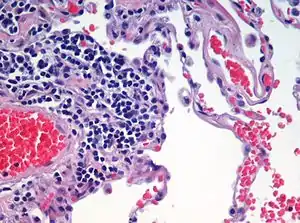

Hematoxylin principally colors the nuclei of cells blue or dark-purple,[6][15][14] along with a few other tissues, such as keratohyalin granules and calcified material. Eosin stains the cytoplasm and some other structures including extracellular matrix such as collagen[5][7][14] in up to five shades of pink.[8] The eosinophilic (substances that are stained by eosin)[5] structures are generally composed of intracellular or extracellular proteins. The Lewy bodies and Mallory bodies are examples of eosinophilic structures. Most of the cytoplasm is eosinophilic and is rendered pink.[10][15] Red blood cells are stained intensely red.

Ductal carcinoma in situ (DCIS) in breast tissue, cell nuclei (blue-purple), extracellular material (pink). Lung tissue taken from an emphysema patient. Cell nuclei (blue-purple), red blood cells (bright red), other cell bodies and extracellular material (pink), and air spaces (white).

Lung tissue taken from an emphysema patient. Cell nuclei (blue-purple), red blood cells (bright red), other cell bodies and extracellular material (pink), and air spaces (white). Muscle tissue, cell nuclei (blue-purple), cell body (pink).